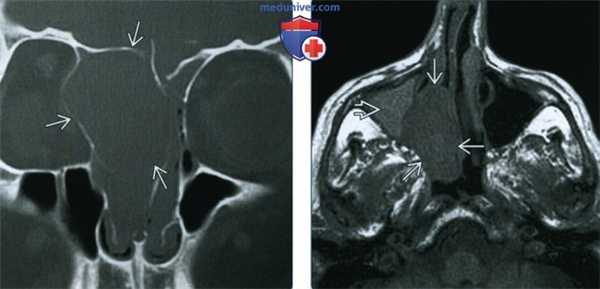

(Слева) При корональной костной КТ в полости носа и решетчатом лабиринте слева определяется экспансивное объемное образование. Обратите внимание на легкое ремоделирование окружающих костей, позволяющее сделать вывод о доброкачественности образования (шванномы), которое ошибочно может быть принято за мукоцеле.

(Справа) При аксиальной МРТ Т1 в полости носа справа определяется шваннома, смещающая носовую перегородку влево. В верхнечелюстной пазухе снаружи от образования находится «запертый» секрет с гиперинтенсивным сигналом.